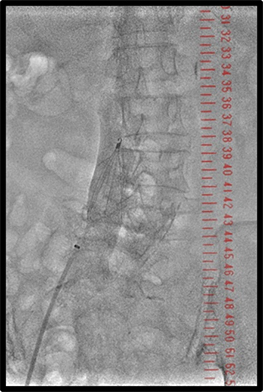

その他、当院で実際に使用した臨床例について示す。(図10、図11、図12)

IGS630_Fukaya_13.jpg図10 IVUSマーキング